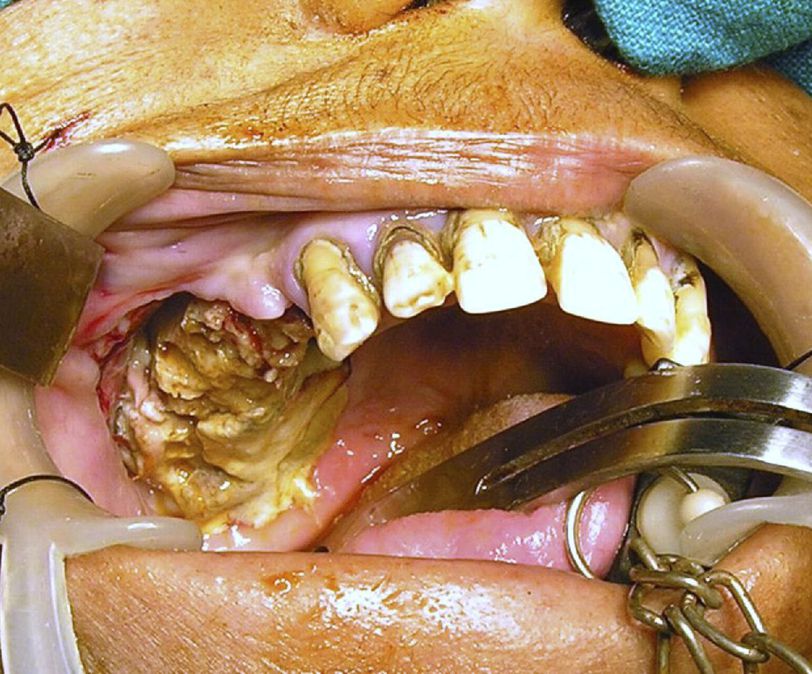

A 52 year old lady presented to emergency department with severe pain in right maxillary region after 1 week of the extraction of premolars and molars. The pain aggravated on bending forward and was not associated with any swelling, ulceration or foul smell. However, she complained of partial right nasal obstruction. On examination, there was a large necrotic area in right maxilla which began from canine anteriorly and went beyond maxillary tuberosity posteriorly. The patient was having a fever of 100.7°F with a raised blood pressure upto 160/90. Rest of the examination was unremarkable. A number of differentials including tuberculous osteomyelitis, tertiary syphilis, necrotizing sialometaplasia , squamous cell carcinoma, mucormycosis, aspergillosis and adenoid cystic carcinoma were made. After conducting a number of labs and VDRL tests, radiological investigations were carried out. The CT scan showed a large area of alveolar destruction involving some portion of right nasal cavity as well as extension to right ethmoidal and sphenoidal sinuses. No cranial or orbital involvement was seen. Histopathological examination revealed septate aspergillus hyphae along with large necrotic and inflammatory tissues. A diagnosis of aspergillosis was made and patient was given intravenous Amphotericin B 0.8/mg/kg/day. Under General Anesthesia, excision of complete right maxillary sinus as well as lateral wall of right nasal cavity was conducted and the patient was put on antifungal therapy for 6 weeks. References: Patil, P. M., & Bhadani, P. (2011). Extensive Maxillary Necrosis Following Tooth Extraction. Journal of Oral and Maxillofacial Surgery, 69(9), 2387-2391. doi:10.1016/j.joms.2010.11.018